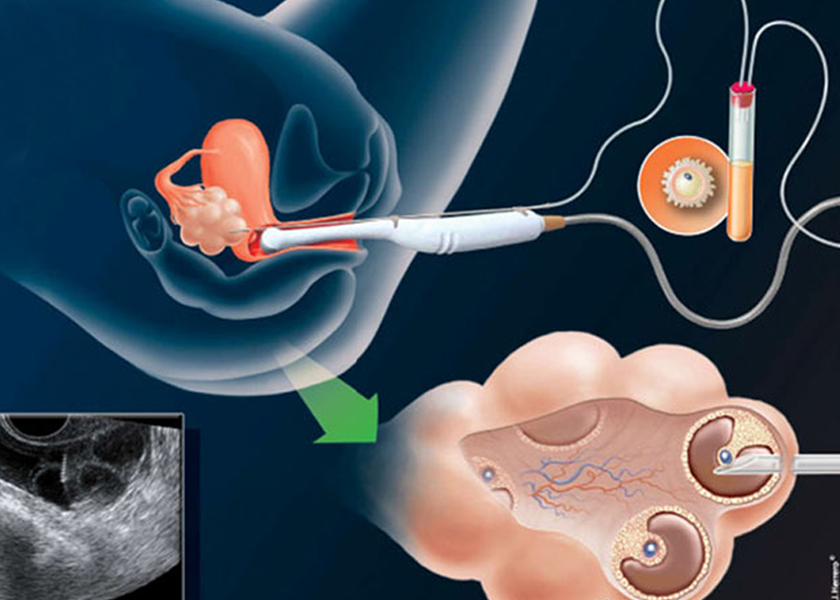

প্রেগন্যান্সি চাইলে ডাক্তারের পরামর্শ নিয়ে ওরাল মেডিসিন নেওয়া বন্ধ করতে হবে। এরপর যদি অন্তঃসত্ত্বা হতে কোনো অসুবিধা হয় তাহলে ডাক্তারের কাছে গিয়ে প্রয়োজনীয় চিকিৎসা করে নিলেই সমস্যার সমাধান হবে। অনিয়মিত ডিম্বাণু বেরনোকে নিয়মিত করে দিলেই ভবিষ্যতে মা হতে আর কোনও অসুবিধা থাকবে না। তবে পলিসিস্টিকের সঙ্গে ওবেসিটি থাকলে বিষয়টি জটিল হতে পারে। তাই মা হতে চাইলে আগে ওজন কমাতে হবে। এই রোগীদের প্রেগন্যান্সির সময় ব্লাড সুগার ও ব্লাড প্রেশার বাড়তে পারে। এছাড়া অন্য সমস্যা হলে সিস্টগুলিকে পাংচার (ড্রিলিং) করে দেওয়া হয়। তাতে সাময়িকভাবে ডিম্বাণু নিঃসৃত হতে পারে। তবে এখন এত আধুনিক ওষুধ বেরিয়েছে যে ড্রিলিং করার দরকার হয় না।